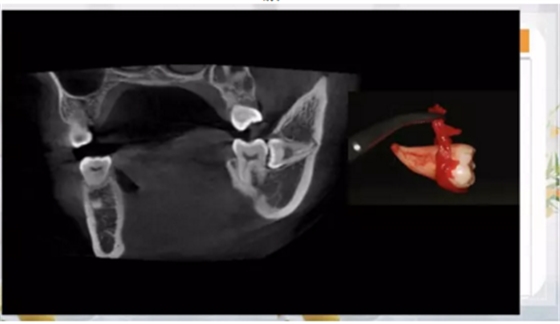

如何才能完整而且沒有骨損傷的拔掉這顆牙齒呢?

那就兩個(gè)一起拔!

其實(shí)是這樣的!